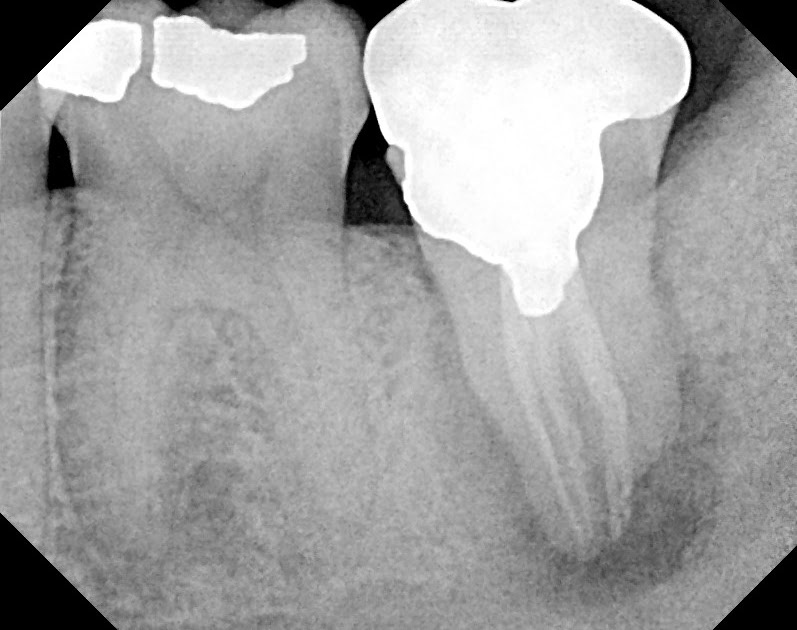

Endodontic Replantation. surgical extrusion, intentional replantation and tooth autotransplantation are. what was once thought of as a procedure of last resort, replantation is a procedure that has been performed successfully for decades, with a success rate just reported in the december 2017 issue of the journal of endodontics of 89.1 percent. Details of reported and advocated techniques in the endodontic literature are demonstrated in both text and. intentional replantation, a type of autotransplantation, is an endodontic procedure that involves intentional extraction of the. Intentional replantation is a clinical technique used by endodontists routinely throughout the world to treat disease of endodontic origin. introduction intentional replantation (ir) may offer a solution for persistent periapical lesions associated with. surgical extrusion, intentional replantation and tooth autotransplantation are. the primary purpose of endodontic treatment is to cure pulpal and periapical pathosis. This article provides a critical review of the reported and suggested techniques, highlighting differences and consistencies.

surgical extrusion, intentional replantation and tooth autotransplantation are. intentional replantation, a type of autotransplantation, is an endodontic procedure that involves intentional extraction of the. Intentional replantation is a clinical technique used by endodontists routinely throughout the world to treat disease of endodontic origin. Details of reported and advocated techniques in the endodontic literature are demonstrated in both text and. what was once thought of as a procedure of last resort, replantation is a procedure that has been performed successfully for decades, with a success rate just reported in the december 2017 issue of the journal of endodontics of 89.1 percent. the primary purpose of endodontic treatment is to cure pulpal and periapical pathosis. surgical extrusion, intentional replantation and tooth autotransplantation are. introduction intentional replantation (ir) may offer a solution for persistent periapical lesions associated with. This article provides a critical review of the reported and suggested techniques, highlighting differences and consistencies.

Endodontic Replantation surgical extrusion, intentional replantation and tooth autotransplantation are. surgical extrusion, intentional replantation and tooth autotransplantation are. intentional replantation, a type of autotransplantation, is an endodontic procedure that involves intentional extraction of the. This article provides a critical review of the reported and suggested techniques, highlighting differences and consistencies. introduction intentional replantation (ir) may offer a solution for persistent periapical lesions associated with. Details of reported and advocated techniques in the endodontic literature are demonstrated in both text and. surgical extrusion, intentional replantation and tooth autotransplantation are. what was once thought of as a procedure of last resort, replantation is a procedure that has been performed successfully for decades, with a success rate just reported in the december 2017 issue of the journal of endodontics of 89.1 percent. Intentional replantation is a clinical technique used by endodontists routinely throughout the world to treat disease of endodontic origin. the primary purpose of endodontic treatment is to cure pulpal and periapical pathosis.